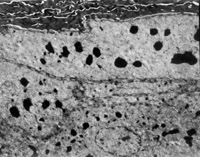

É˺ó12h¼±ÕïÈëÔº£¬£¬ £¬£¬£¬£¬£¬£¬¼ì²éË«ÏÂ֫Ϊdz¢ó¶ÈÉÕÉË ¡£¡£¡£¡£¡£¡£ ¡£¡£´´Ãæ±íƤÒÑ»µËÀ°þÍÑ£¬£¬ £¬£¬£¬£¬£¬£¬ÕæÆ¤²ã±äÐÔ»µËÀ³ÊÀ¯»ÆÉ«ºÍÀ¯°×É«Ïà¼ä£¨Í¼5-3-1£© ¡£¡£¡£¡£¡£¡£ ¡£¡£È¡¾Ö²¿×éÖ¯×ö²¡ÀíÇÐÆ¬¼ì²é£¬£¬ £¬£¬£¬£¬£¬£¬ÏÔʾÉÏÆ¤×é֯ȫ²ã»µËÀ£¬£¬ £¬£¬£¬£¬£¬£¬ÕæÆ¤²ã½ºÔ­ÏËά±äÐÔ£¬£¬ £¬£¬£¬£¬£¬£¬½á¹¹ÔÓÂÒ£¬£¬ £¬£¬£¬£¬£¬£¬Î¢Ñ­»·ðöÖÍ£¨Í¼5-3-2£© ¡£¡£¡£¡£¡£¡£ ¡£¡£

5-3-2 ÉÏÆ¤×é֯ȫ²ã»µËÀ£¬£¬ £¬£¬£¬£¬£¬£¬½ºÔ­ÏËά±äÐÔ£¬£¬ £¬£¬£¬£¬£¬£¬Î¢Ñ­»·ðöÖÍ HE¡Á20